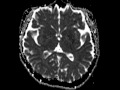

Choroid Plexus Xanthogranuloma

These images show a T2 hyperintense, T2 FLAIR hyperintense, T1 hypointense, non-enhancing mass in the atrium of the right lateral ventricle which is bright on diffusion weighted imaging and has a central area of low ADC value compatible with restricted diffusion. The differential diagnosis may include a parasitic cyst, arachnoid cyst, or choroid plexus cyst or xanthogranuloma. This is a choroid plexus xanthogranuloma which is thought to result from cystic degeneration of the choroid plexus with possible hemorrhage which ultimately fills with cholesterols crystals, calcific deposits, and macrophages resulting in a gelatinous cyst. The restricted diffusion is likely secondary to the high protein content and should not be confused for a neoplasm.